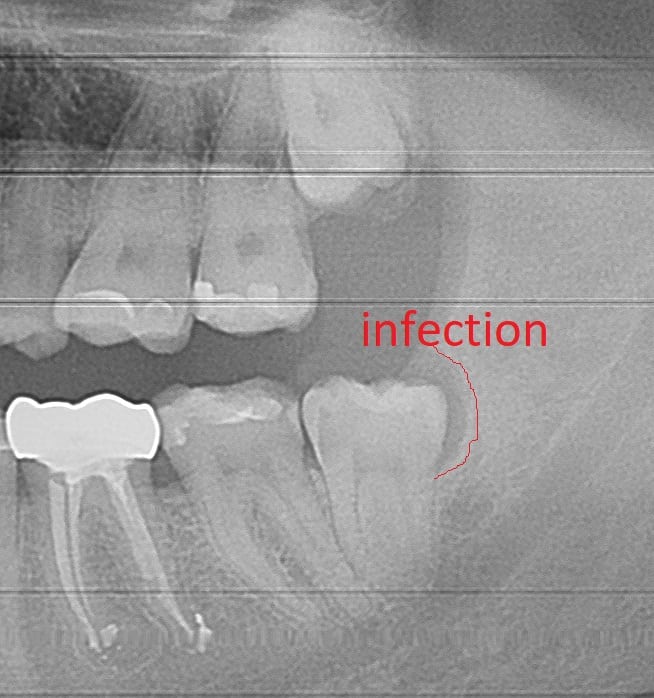

Can Wisdom Teeth Cause cavities in adjacent teeth?

Food impaction caused by wisdom teeth can create cavities in the wisdom tooth.  Cavities can also affect the adjacent nearby tooth.  This may result in significant tooth damage to the second molar tooth directly next to the wisdom tooth.  The second molar may require a filling, root canal or in some circumstances may have to get extracted because of the severe damage.

Cavities cause tooth pain when they extend deep inside the tooth reaching the nerves.  In many situations food impaction can also cause cavities in the adjacent tooth.

More pictures of wisdom teeth with cavities can be found in our tooth extraction gallery

wisdom tooth cavities

Food impaction caused extensive cavities in the tooth adjacent to the bottom wisdom tooth, requiring a root canal.